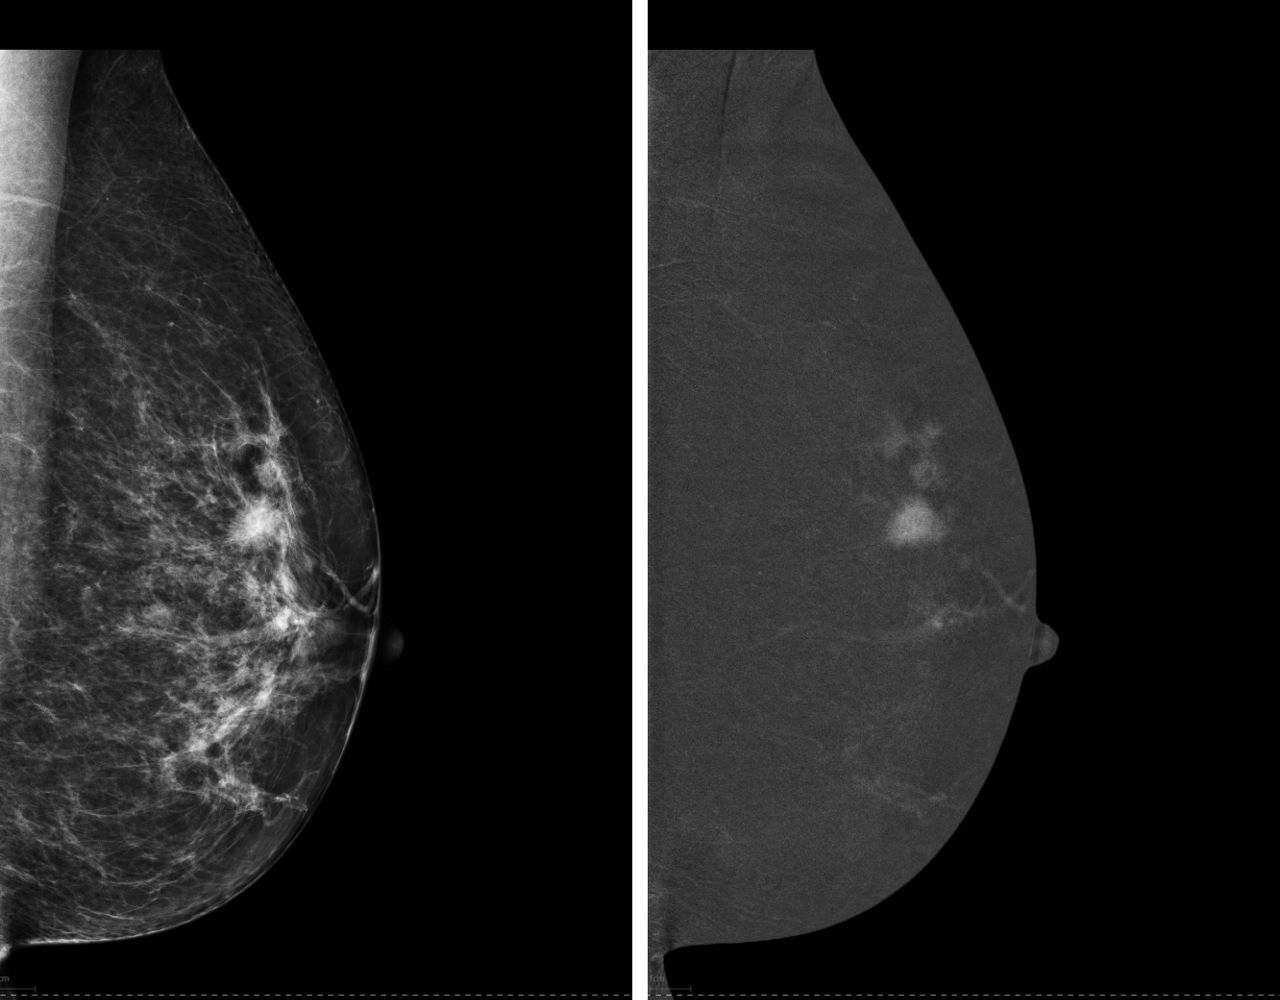

Mammography Clinical Applications Training

Our collaborative and customized approach to your training plan optimizes every aspect of learning to help you improve workforce effectiveness, asset utilization, and patient flow.